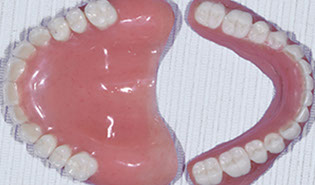

Step 3 – "Test-drive" your temporary tooth restorations

Brener Clinic custom-makes and places temporary tooth restorations and replacements for you to "test-drive". These mock-up restorations are derived using the DSD data and look almost exactly the same as your final restorations.

Step 4 – Placing your permanent tooth restorations

Brener Clinic custom-makes and places your permanent tooth restorations and replacements for a beautiful natural new smile.

v) Fabricating temporary and permanent restorations

vi) Placing temporary and permanent restorations for a beautiful new smile